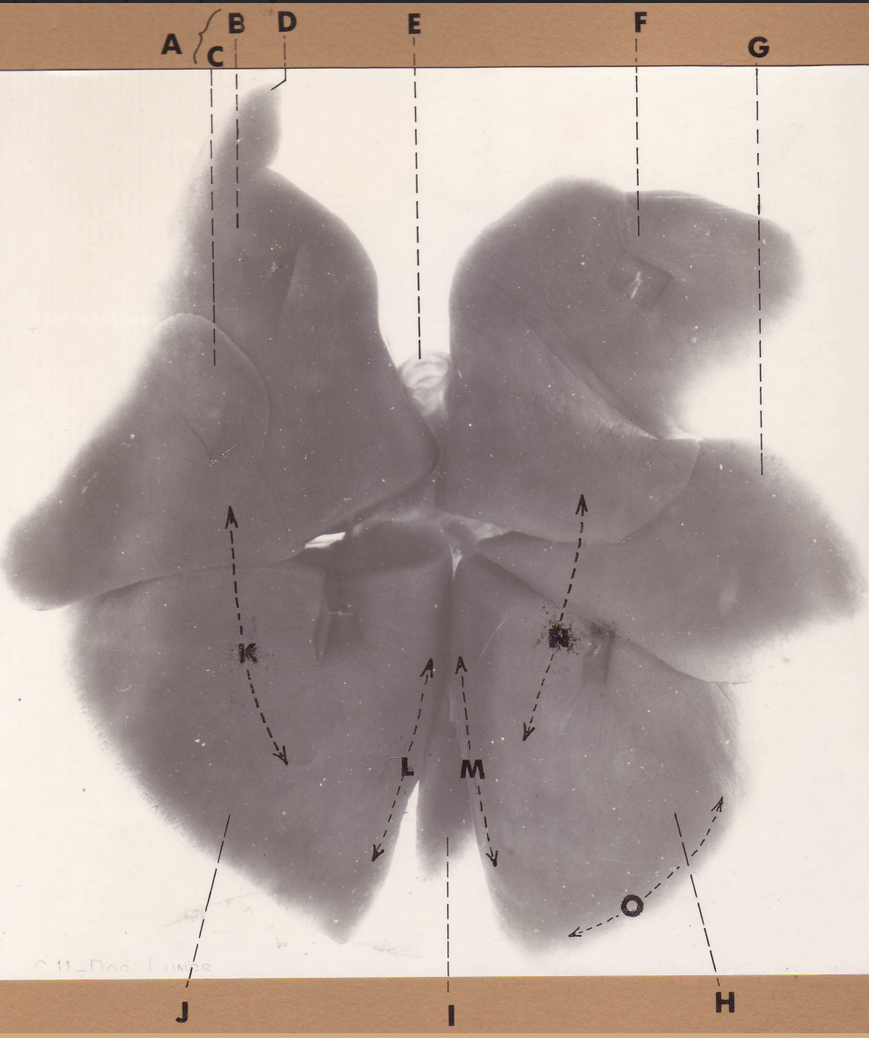

A

(pig lungs, dorsal)

L cranial lobe, caudal segment

B

(pig lungs, dorsal)

L cranial lobe, cranial segment

C

(pig lungs, dorsal)

trachea

D

(pig lungs, dorsal)

R cranial lobe

E

(pig lungs, dorsal)

cardiac notch

F

(pig lungs, dorsal)

middle lobe

G

(pig lungs, dorsal)

dorsal border

H

(pig lungs, dorsal)

costal surface

I

(pig lungs, dorsal)

basal border

J

(pig lungs, dorsal)

R caudal lobe

K

(pig lungs, dorsal)

L caudal lobe

A

(pig lungs, dorsal)

L cranial lobe, caudal segment

B

(pig lungs, dorsal)

L cranial lobe, cranial segment

C

(pig lungs, dorsal)

trachea

D

(pig lungs, dorsal)

R cranial lobe

E

(pig lungs, dorsal)

cardiac notch

F

(pig lungs, dorsal)

middle lobe

G

(pig lungs, dorsal)

dorsal border

H

(pig lungs, dorsal)

costal surface

I

(pig lungs, dorsal)

basal border

J

(pig lungs, dorsal)

R caudal lobe

K

(pig lungs, dorsal)

L caudal lobe